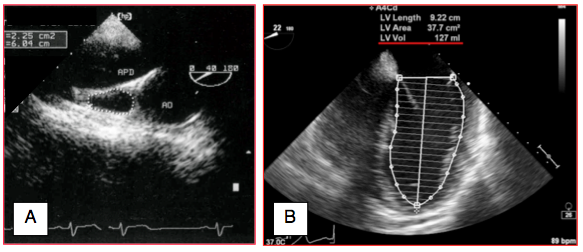

Une mesure plus fiable du volume télédiastolique gauche peut être obtenue par la règle de Simpson: l'endocarde est dessiné au traceur ou par détection automatique des contours avec correction manuelle; la base est déterminée par le plan de l'anneau mitral. La cavité est divisée en 20 disques selon le long-axe du VG par le processeur, qui calcule le volume à partir de la somme de celui de chacun des 20 disques circulaires: V = (π / 4) • (Σ D1 + Σ D2) • (L / n), où n est le nombre de disques (20) et D1 et D2 sont les diamètres des disques dans le plan A et dans le plan B. Cette méthode est la mesure bidimensionnelle la plus appropriée pour le calcul du volume, mais elle doit être appliquée dans deux vues orthogonales (plan A 4-cavités 0° et plan B 2-cavités 90°, par exemple). La règle de Simpson a été bien validée pour calculer la fraction d'éjection, qui est le rapport entre les volumes mesurés, mais non pour calculer la valeur absolue du volume à cause de l'amputation de la partie apicale du VG. D’autres structures peuvent servir de marqueur au remplissage. Par exemple, la surface de la veine cave supérieure (VCS) est ≥ 2 cm2 ; en hypovolémie, elle devient inférieure à 1 cm2 (Figure 27.3).

Figure 27.3 : Evaluation bidimensionnelle de la volémie. A: vue court-axe basale de la veine cave supérieure et mesure de sa surface de section (ici 2.25 cm2). APD: artère pulmonaire droite. B: technique de mesure du volume ventriculaire gauche selon la règle de Simpson (ici 127 mL); l'endocarde est dessiné au traceur ou de manière semi-automatique; la base est déterminée par le plan de l'anneau mitral; la cavité est divisée en 20 disques le long du long-axe du VG. Le processeur calcule le volume à partir de la somme de celui de chacun des 20 disques circulaires.

Une mesure plus fiable du volume télédiastolique gauche peut être obtenue par la règle de Simpson: l'endocarde est dessiné au traceur ou par détection automatique des contours avec correction manuelle; la base est déterminée par le plan de l'anneau mitral. La cavité est divisée en 20 disques selon le long-axe du VG par le processeur, qui calcule le volume à partir de la somme de celui de chacun des 20 disques circulaires: V = (π / 4) • (Σ D1 + Σ D2) • (L / n), où n est le nombre de disques (20) et D1 et D2 sont les diamètres des disques dans le plan A et dans le plan B. Cette méthode est la mesure bidimensionnelle la plus appropriée pour le calcul du volume, mais elle doit être appliquée dans deux vues orthogonales (plan A 4-cavités 0° et plan B 2-cavités 90°, par exemple). La règle de Simpson a été bien validée pour calculer la fraction d'éjection, qui est le rapport entre les volumes mesurés, mais non pour calculer la valeur absolue du volume à cause de l'amputation de la partie apicale du VG. D’autres structures peuvent servir de marqueur au remplissage. Par exemple, la surface de la veine cave supérieure (VCS) est ≥ 2 cm2 ; en hypovolémie, elle devient inférieure à 1 cm2 (Figure 27.3).

Figure 27.3 : Evaluation bidimensionnelle de la volémie. A: vue court-axe basale de la veine cave supérieure et mesure de sa surface de section (ici 2.25 cm2). APD: artère pulmonaire droite. B: technique de mesure du volume ventriculaire gauche selon la règle de Simpson (ici 127 mL); l'endocarde est dessiné au traceur ou de manière semi-automatique; la base est déterminée par le plan de l'anneau mitral; la cavité est divisée en 20 disques le long du long-axe du VG. Le processeur calcule le volume à partir de la somme de celui de chacun des 20 disques circulaires.